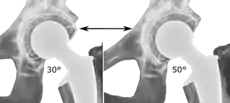

Post-operative projectional radiography is routinely performed to ensure proper configuration of hip prostheses.

The direction of the acetabular cup influences the range of motion of the leg, and also affects the risk of dislocation.[7] For this purpose, the acetabular inclination and the acetabular anteversion are measurements of cup angulation in the coronal plane and the sagittal plane, respectively.